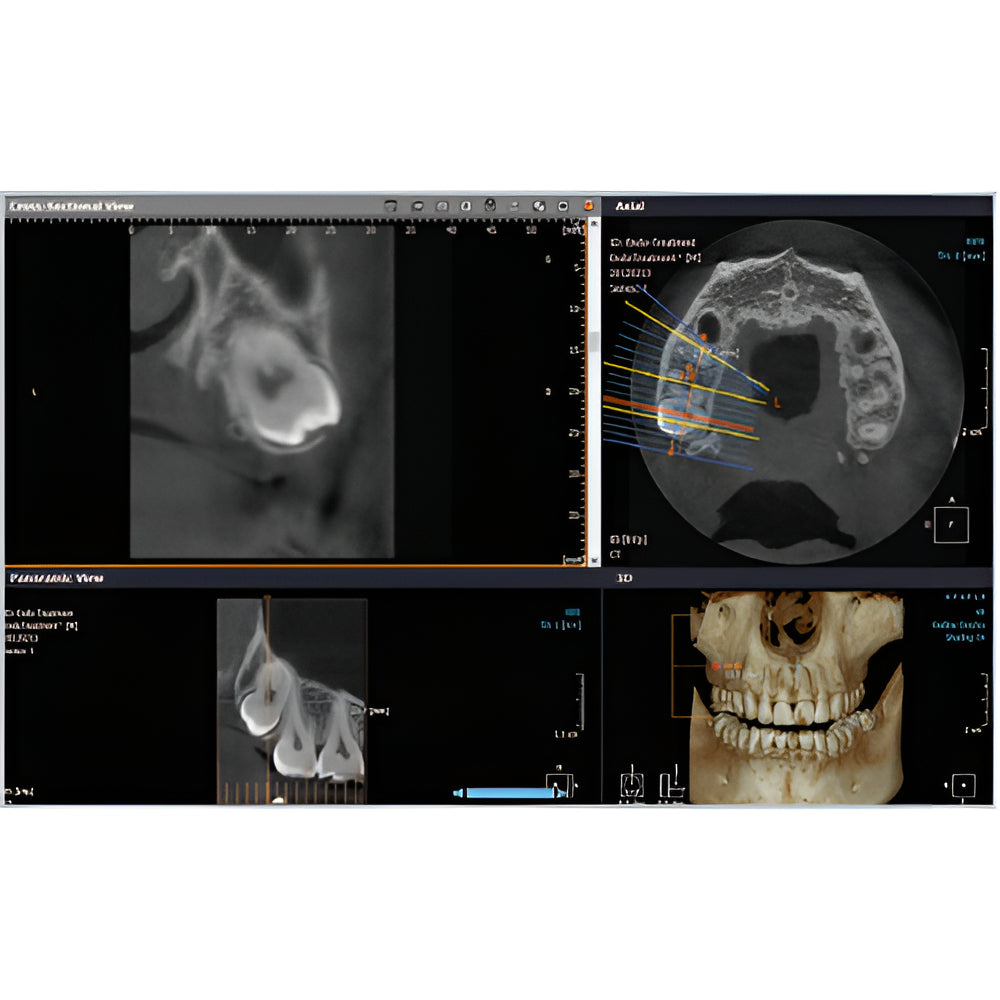

Rayscan Alpha brings another innovative technology with less Recon time and bigger FOV Size. And there are also new features – Fast scan mode, Object scan and Multi FOV.

- Field Of View: 9x9

- 2D/3D Imaging Software with License

- Panoramic

- Multiple Scan Modes